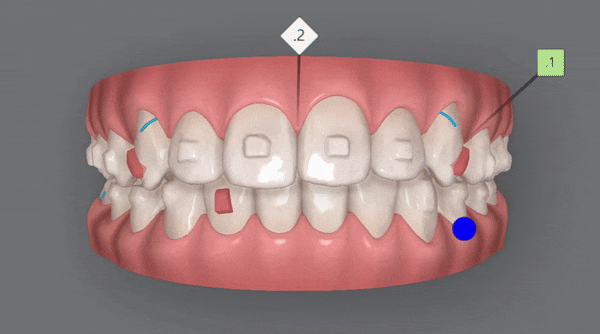

2nd(30개)

치아배열이 어느정도 완성이 되었으나

두번째 클린체크 에서는

이전의 클린체크를 보완해 교정치료의 완성도를 높여 줍니다.

첫번째 클린체크에서는 치아의 배열에 중점을 두었다면

두번째 클린체크에서는 위와 아랫니의 교합을 정돈하기 위한 치료를

진행해드렸습니다 ^^